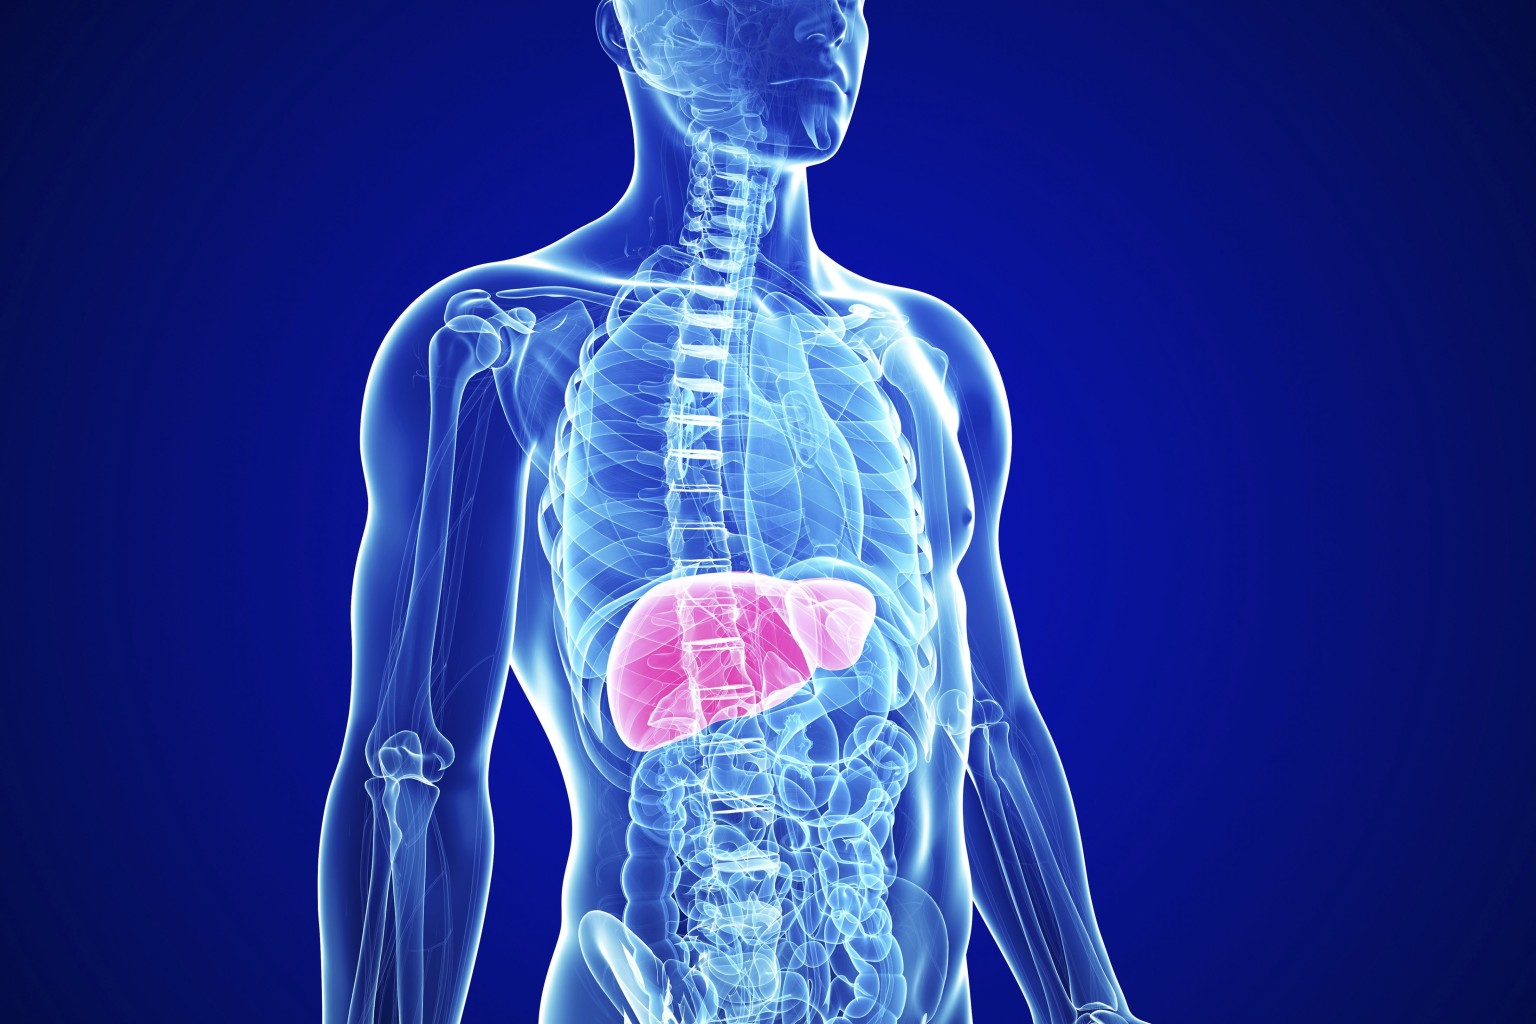

Το ήπαρ είναι ένα από τα πιο σημαντικά όργανα του ανθρωπίνου σώματος.

Βρίσκεται κάτω από το διάφραγμα, στο δεξιό και άνω μέρος της κοιλίας, πλάι στο στομάχι και ακριβώς επάνω από τη χοληδόχο κύστη και το παχύ έντερο.

Ζυγίζει περίπου 1,5 κιλό και είναι το δεύτερο μεγαλύτερο όργανο του ανθρώπινου σώματος.

Το ήπαρ εκτελεί ένα ευρύ φάσμα λειτουργιών στο οποίο περιλαμβάνεται η αποτοξίνωση, η σύνθεση πρωτεϊνών και η παραγωγή βιοχημικών ουσιών που είναι απαραίτητες για την πέψη των τροφών.

Δείτε τις έξι τροφές που προστατεύουν το ήπαρ:

Η κολλιτσίδα (Burdock Root) ή αρκουδοβότανο ή πλατομαντηλίδα, έχει έντονη καταπραϋντική και αντιμικροβιακή δράση. Είναι πλούσια σε ινσουλίνη, ένα φυτικό πολυσακχαρίτη, που βοηθά την εντερική λειτουργία και απομακρύνει τις τοξίνες από το ήπαρ.

Η πικραλίδα (ή ταραξάκο), αποτοξινώνει το ήπαρ, μειώνει τον μετεωρισμό και συμβάλλει στην πρόληψη παθήσεων του πεπτικού συστήματος.

Το κόκκινο λάχανο περιέχει πολυφαινόλες, βιταμίνες Α και C και η συχνή κατανάλωσή του ενισχύει το ανοσοποιητικό σύστημα. Το κόκκινο λάχανο είναι επίσης πλούσιο σε γλυκοσινολάτες, θρεπτικά συστατικά, τα οποία μειώνουν τη φλεγμονή και συμβάλλουν στην αντιμετώπιση του έλκους.

Οι αγκινάρες είναι πλούσιες σε κυανίνη, μια φυτική ένωση, η οποία συμβάλλει στην αναγέννηση του ήπατος και βελτιώνει τη λειτουργία της χοληδόχου κύστης. Η συχνή κατανάλωσή τους, ενισχύει την όραση και αυξάνει την οστική πυκνότητα.

Το λεμόνι είναι πλούσιο σε βιταμίνη C, η οποία έχει έντονη αντιοξειδωτική δράση και αποτοξινώνει το ήπαρ, μειώνει τον ανώμαλο πολλαπλασιασμό των κυττάρων και συμβάλλει στη διατήρηση της υγείας της ουροδόχου κύστης.

Τα πράσινα φυλλώδη λαχανικά, είναι πλούσια σε γλυκοσινολάτες, συστατικά που απομακρύνουν τις τοξίνες από το ήπαρ, βελτιώνουν την υγεία του εντέρου και βοηθούν τις κενώσεις.